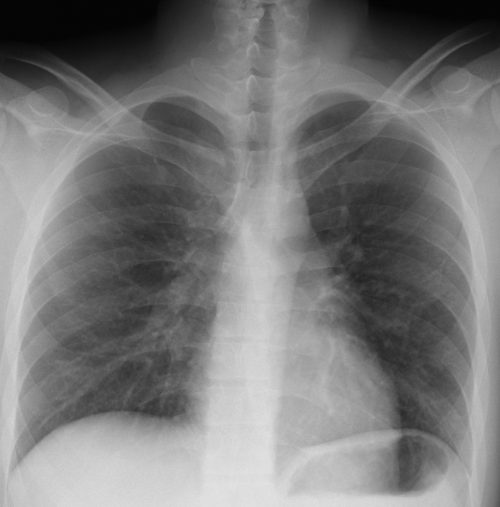

[注意] 心陰影にみえる肺門陰影(右)、シルエットサイン陰性に気づけば肺炎像と理解できる。また、左肺門部陰影は心辺縁が不鮮明(シルエットサイン陽性)で同部にも浸潤影があることが推定できる。 肺門部の浸潤影はいつも慎重に判断する必要がある。下写真の左肺門部の心陰影ははっきりせず(左上挿入写真は治癒時)判断に迷うがシルエット陽性と判断すればS6もしくはS3の肺炎が推定可能になる。下の写真はS6の浸潤影が想定される。 [肺門の陰影]

左は肺門の変化からマイコプラズマ肺炎と診断、オゼックス投与にて解熱しないため3日後に確認したところ浸潤影が拡大していた。 [心陰影の把握]